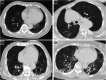

Figures